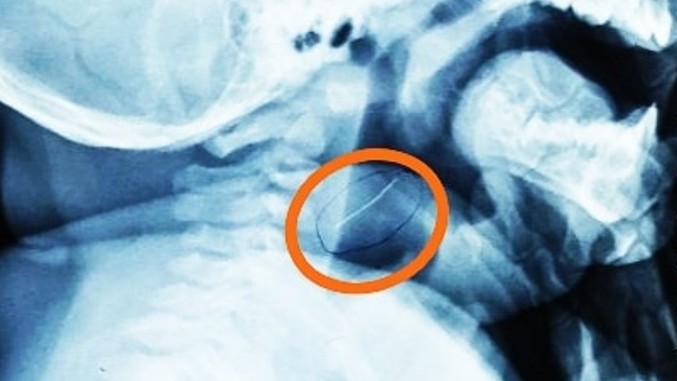

Em bé thủng họng vì sợi kim loại trong cháo

Hướng dẫn nuôi dạy con -  30/01/2021

Khi đang ăn cháo cá, bệnh nhi bỗng quấy khóc, bỏ ăn và nôn ra cháo, lẫn một ít nhầy nhớt. Sợ bé bị hóc xương, người nhà đưa ngay vào Bệnh viện Nhi đồn...